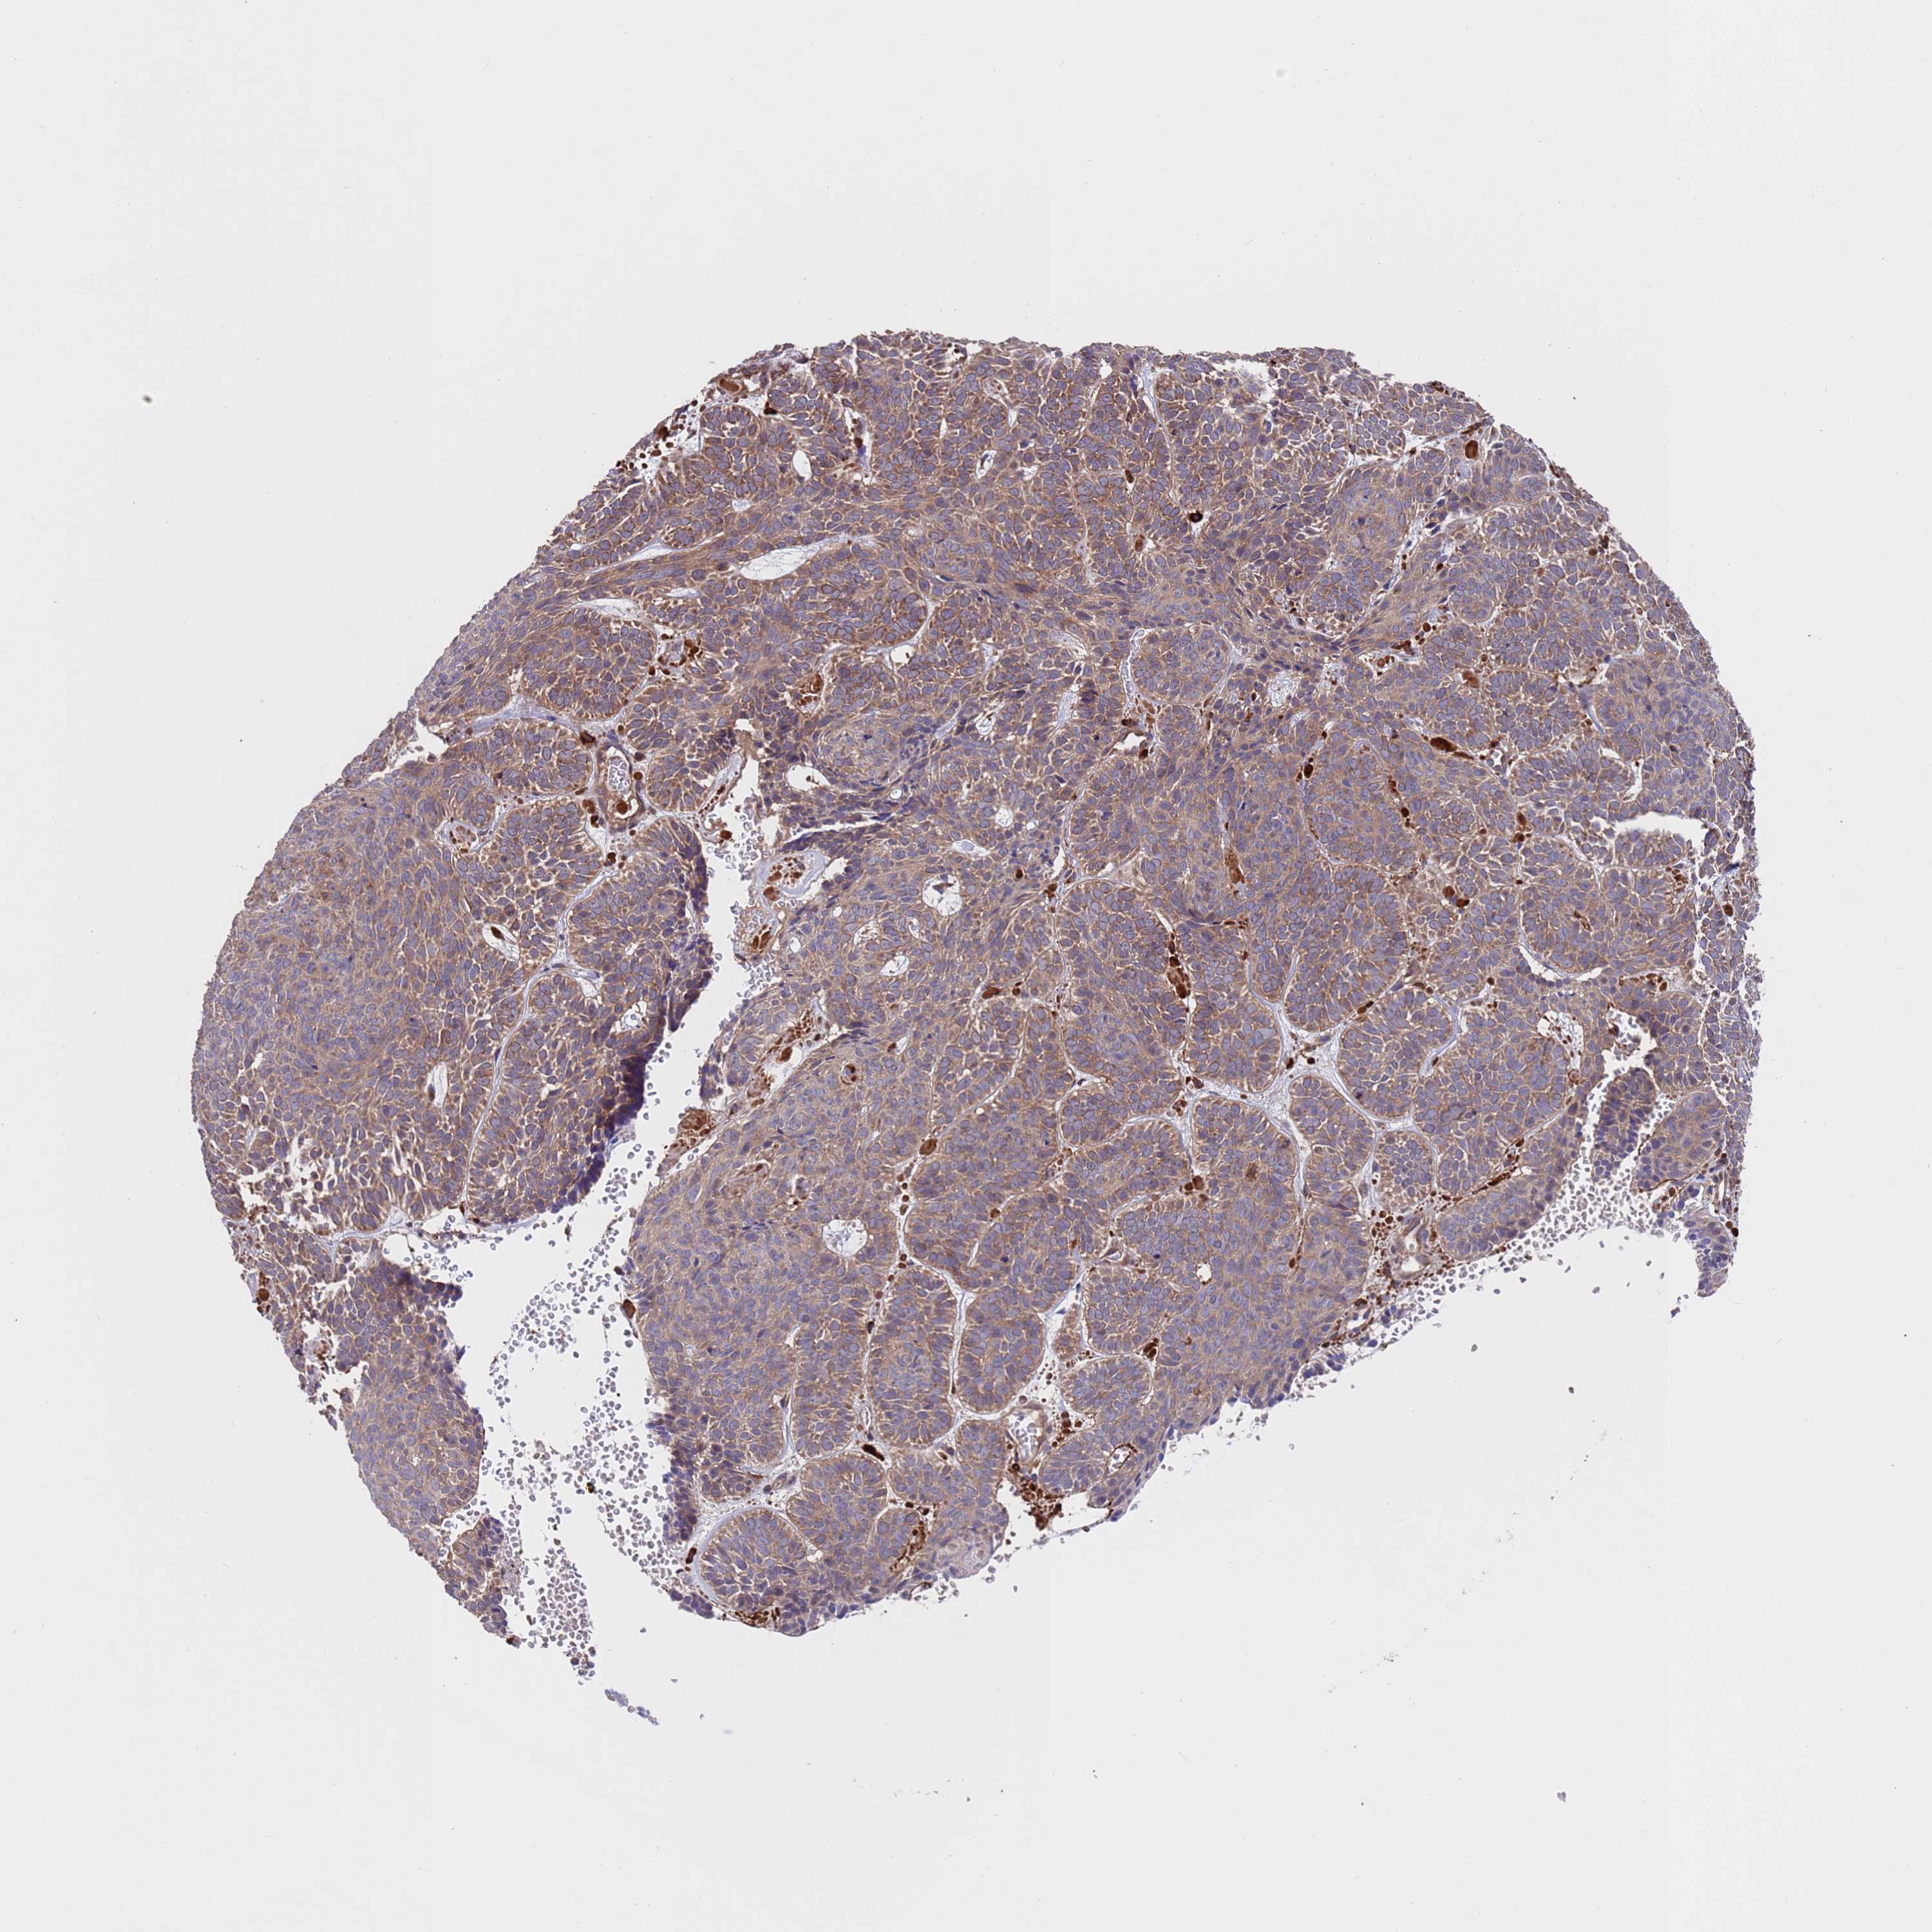

SKIN CANCER - Protein expressioni

A mouse-over function shows sample information and annotation data. Click on an image to view it in a full screen mode. Samples can be filtered based on level of antibody staining by selecting one or several of the following categories: high, medium, low and not detected. The assay and annotation is described here.

Each image is clickable and will lead to virtual microscopy that enables deeper exploration of all samples and also displays staining intensity scores, fraction scores and subcellular localization as well as patient and tissue information for each sample.

Antibody HPA046265

Staining

High

Medium

Low

Not detected

Intensity

Strong

Moderate

Weak

Negative

Quantity

>75%

75%-25%

<25%

None

Location

Nuclear

Cytoplasmic/membranous

Cytoplasmic/membranous,nuclear

Squamous cell carcinoma, NOS

Squamous cell carcinoma, metastatic, NOS

Basal cell carcinoma